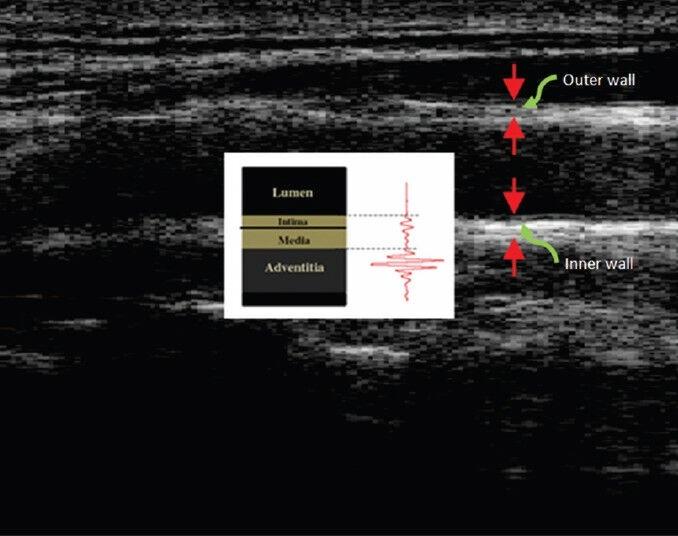

Quantification of arterial elasticity and its dependency to age is considered in this paper. We use radiofrequency (RF) signals from carotid artery ultasonography to evaluate this dependency. Blood pressure, blood flow, and tethering to surrounding tissue are the main causes of the motion of the carotid wall. Tracking carotid artery wall motion from a series of ultrasound B-mode images is challenging due to the presence of noise and variable contrast. Moreover, the process of converting RF signals into the B-mode images causes some information to be lost. Hence, our goal is to extract the carotid wall motions and vibrations from RF signals. After extraction and removing the wall motion by using the phased tracking method combined with continuous wavelet transform, the vibrations of carotid inner wall in different subjects in different ages are compared with each other. Empirical mode decomposition method is used for extracting the first intrinsic mode function for different subjects' vibration and then their zero-crossing rates are compared. The results show the vibrations of the carotid inner wall are clearly decreased by age.

本文探讨了动脉弹性的量化及其与年龄的关系。我们利用颈动脉超声检查的射频(RF)信号来评估这种关系。血压、血流以及与周围组织的附着是颈动脉壁运动的主要原因。由于存在噪声和对比度变化,从一系列超声B模式图像中跟踪颈动脉壁运动具有挑战性。此外,将RF信号转换为B模式图像的过程会导致一些信息丢失。因此,我们的目标是从RF信号中提取颈动脉壁的运动和振动。在使用相位跟踪方法结合连续小波变换提取并去除壁运动后,比较不同年龄组不同受试者颈动脉内壁的振动。采用经验模态分解方法提取不同受试者振动的第一个固有模态函数,然后比较它们的过零率。结果表明,随着年龄的增长,颈动脉内壁的振动明显减弱。